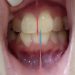

Nghiên cứu ứng dụng phương pháp đóng khoảng bằng vít neo (mini-screws) phối hợp với dây thép chữ nhật có bẻ móc dạng chiếc giày ( shoe hooks) trong điều trị chỉnh hình giảm hô- xương – răng nặng có nhổ răng